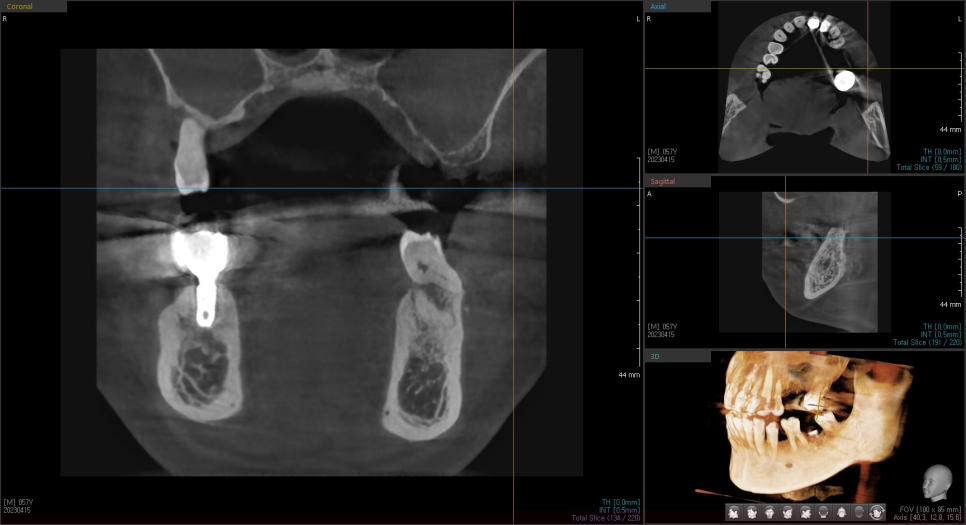

23.04.15

평면적인 정보 말고

앞뒤 좌우 3차원적인 자세한 분석을 위해

ct 촬영을 시행

디지털 기기의 분석 결과

3mm 정도의 아주 얇은 뼈가 확인되었습니다.

23.05.20

상악동 거상술을 동반한

상일동 임플란트 완료 사진입니다.

뼈가 월드컵 경기장 모양처럼

돔 형태로 이식이 된 게 확인됩니다.

이제 임플란트가 뼈에 잘 붙기를

기다리는 시간만 남았습니다.

환자분에 따라 치유 기간은 다르지만

상악동 거상술을 한 경우 적어도 4개월,

길게는 6~8개월까지의 시간을 기다립니다.